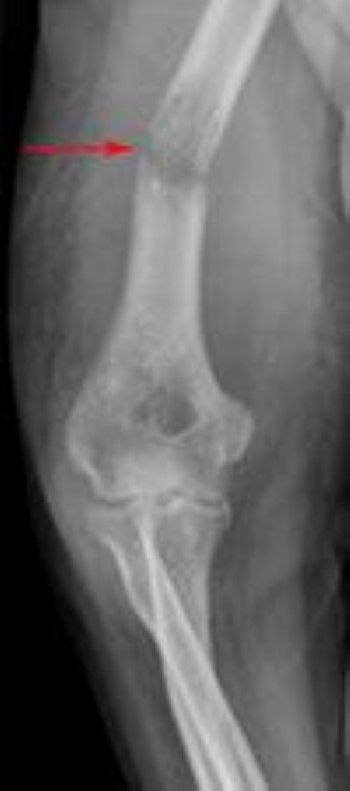

Breast Cancer Metastatic To C Spine Musculoskeletal Case Studies